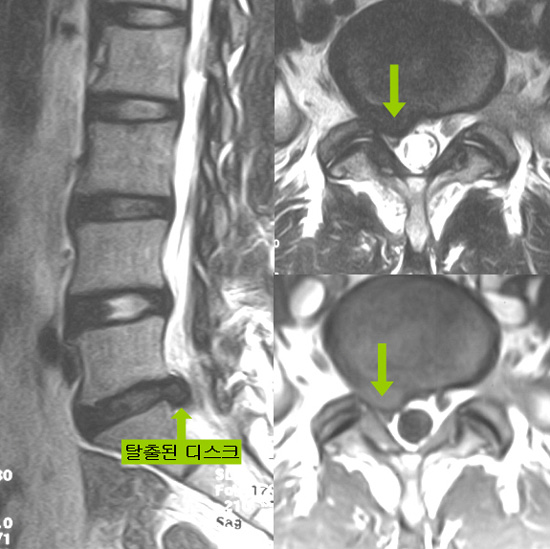

요추 추간판 탈출증(허리디스크)은 허리 부위의 추간판(디스크)이 손상되거나 탈출하여 인근 신경을 압박하는 상태를 말합니다.

이는 주로 하중을 많이 받는 요추 부위(L1~L5)에서 발생하며, 심한 경우 허리와 다리의 통증 및 감각 저하를 초래할 수 있습니다.

증상은 탈출된 디스크의 위치와 압박된 신경에 따라 다를 수 있습니다.